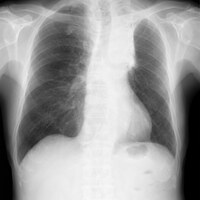

食欲が増えて両足の冷えが治り、体力が回復した肺がん患者。1週間で子宮筋腫がほとんど消えて、便通が良くなり、冷え性が治った女性。 | 本場の中国鍼 李哲鍼灸院のブログ

こんにちは、李哲です。 アメリカの著名な中医師、倪海厦(ニハイシャ)先生の2005-5-31の治療例を翻訳しました。 肺がんと子宮筋腫の治療内容が書かれています。特に1週間で子宮筋腫がほとんど消えた例は、私が見てもビックリします。鍼治療では